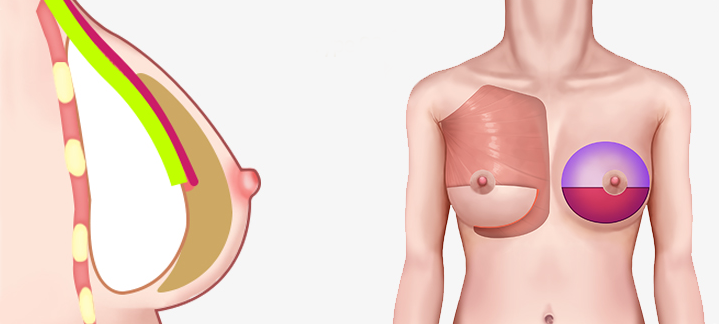

เทคนิคแบบ Dual Plane แบ่งออกเป็น 3 ประเภทใหญ่ ๆ ขึ้นอยู่กับระดับของการสร้างพื้นที่ใต้เยื่อหุ้มเซลล์

โดยเสริมซิลิโคนที่ด้านบนของกล้ามเนื้อและด้านล่างของเนื้อเยื่อ ทำให้มีลักษณะคล้ายกับซิลิโคนมากที่สุด

สามารถสร้างรูปร่างของหน้าอกได้ การเคลื่อนย้ายของซิลิโคนหรือรูปร่างของหน้าอกจะไม่เปลี่ยนแปลง

เมื่อเสริมซิลิโคนใต้กล้ามเนื้อ ความเจ็บปวดจะน้อยกว่ามาก การกลับมาทำงานปกติจะเร็วขึ้น และเยื่อหุ้มสมอง

การเพิ่มชั้นเดียวสามารถปรับปรุงการสะท้อนของซิลิโคน และการสัมผัสจะคล้ายกับการสัมผัสของหน้าอกจริง ๆ

โดยเสริมซิลิโคนใต้กล้ามเนื้อ และเหนือกล้ามเนื้อ อัตราการเกิดการสร้างทรงกลมต่ำกว่าการเสริมแบบมีสายมาก

สามารถสร้างสัมผัสตามธรรมชาติและเส้นใต้เต้านมได้ การเปลี่ยนแปลงรูปร่างมีน้อย

วิธีการใส่ท่อนบนของซิลิโคนลงไปใต้กล้ามเนื้อ และท่อนล่างลงไปใต้เยื่อกล้ามเนื้อ

มักจะใช้กล้ามเนื้อปิดเนื้อเยื่อบางๆของผิวหนัง เพื่อให้เห็นซิลิโคน และความกังวลน้อยลง

เนื่องจากความกดดันของกล้ามเนื้อ จึงมีความเสี่ยงน้อยที่ตำแหน่งของซิลิโคนจะเคลื่อนที่ได้ และความน่าจะเป็นที่จะเกิดคลื่นริ้วรอยก็มีน้อยด้วย

บริเวณที่มีกล้ามเนื้อจะมีผิวหนังและเนื้อเยื่ออ่อนที่ยืดไม่ค่อยออก แต่บริเวณที่ไม่มีกล้ามเนื้อปกคลุมนั้นค่อนข้างที่จะ

ผิวหนังและเนื้อเยื่อที่เชื่อมต่อกันจะยืดได้ดีและช่วยให้เส้นโค้งธรรมชาติยังคงอยู่แม้ในกรณีที่ด้านล่างของหน้าอกแน่นมาก

วิธีการใส่ซิลิโคนบนกล้ามเนื้อ ,ใส่ซิลิโคนใต้เนื้อเยื่อ

เป็นวิธีการผ่าตัดที่เสริมข้อเสียของวิธีใช้สายเดรนและวิธีใช้กล้ามเนื้อ และรวมข้อดีเข้าด้วยกัน

เป็นวิธีการผ่าตัดสามารถสร้างรูปร่างตามธรรมชาติได้

ไม่เหมาะสำหรับเนื้อเยื่อใต้ผิวหนัง (ไขมัน) น้อย

ส่วนที่มีกล้ามเนื้อจะไม่ค่อยยืดออก